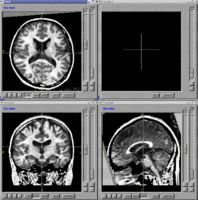

- BRAINSMush - Tool to combine T1 and T2 datasets into a composite image. The resulting image is then used to perform brain extraction. NITRC Link

- BRAINS Auto Workup - Fully automated image analysis pipeline for generation of volumetric measurements. NITRC Link